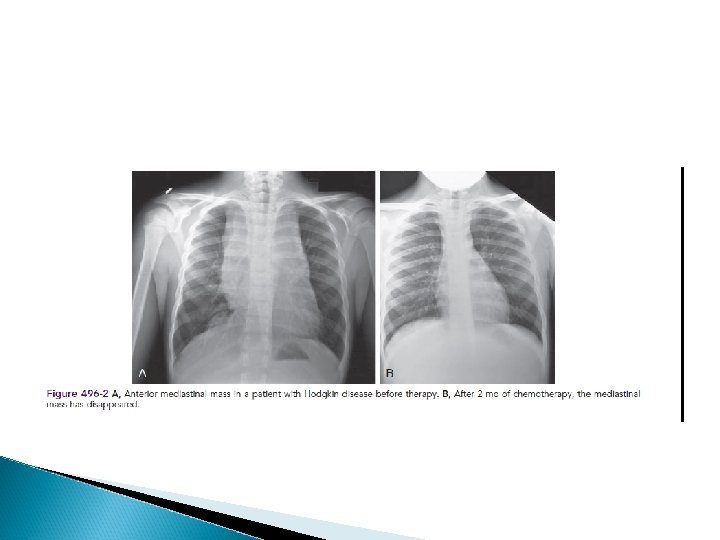

DIAGNOSIS Any patient with persistent, unexplained lymphadenopathy unassociated with an obvious underlying inflammatory or infectious process should undergo chest radiography to identify the presence of a large mediastinal mass before undergoing lymph node biopsy. Formal excisional biopsy is preferred over needle biopsy to ensure that adequate tissue is obtained, both for light microscopy and for appropriate immunohistochemical and molecular studies

A cxr is particularly important for measuring the size of the mediastinal mass in relation to the maximal diameter of the thorax This determines “bulk”disease and becomes prognostically significant. Chest CT more clearly defines the extent of a mediastinal mass if present and identifies hilar nodes and pulmonary parenchymal involvement, which may not be evident on chest radiographs.

A complete response : the complete resolution of disease on clinical examination and imaging studies or at least 70 -80% reduction of disease and a change from initial positivity to negativity on either gallium or PET scanning because residual fibrosis is common

TREATMENT Chemotherapy and radiation therapy Treatment is risk adapted and involves the use of combined chemotherapy with or without low-dose involved-field radiation therapy based on response. Treatment is determined largely by disease stage, presence or absence of B symptoms, and the presence of bulky nodal disease.